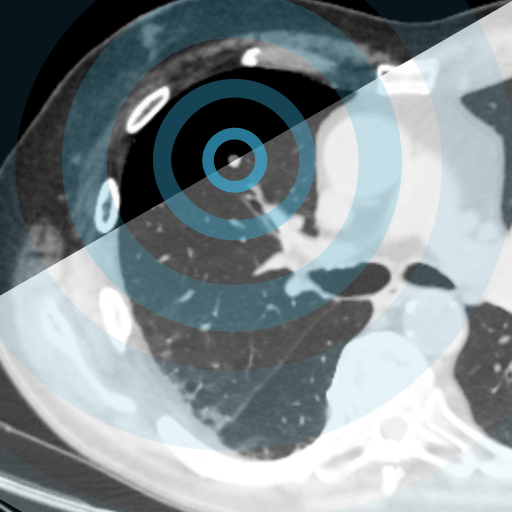

COVID-19 on Chest CT and X-ray

Our COVID-19 content is for healthcare professionals wishing to accurately diagnose COVID-19 on chest X-ray and CT scans. It trains users to identify the presence and severity of the infection, and to differentiate these from other conditions that may present in a similar manner.